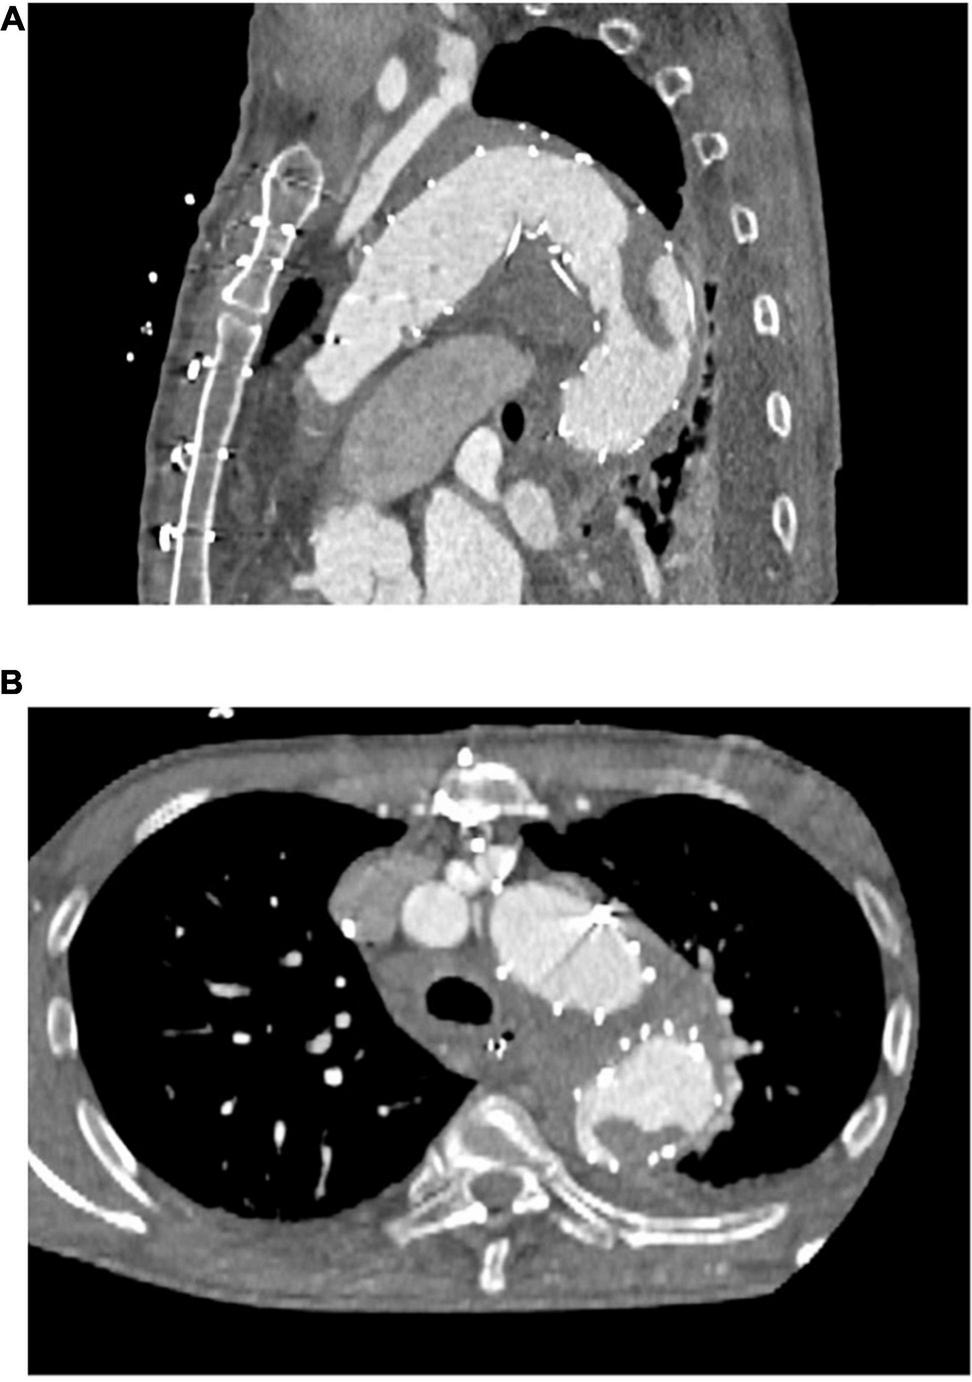

As Table 2 shows, our primary arterial cannulation was the right subclavian artery in most patients. Most concomitant procedures concerned the aortic root or valve. Beating heart technique was applied in almost one third of the patients. There were no statistically significant differences between the two groups. Of the patients with a new in-stent thrombus, one underwent the FET technique after previous thoracic endovascular aortic repair (TEVAR) with no thrombus visible in preoperative CTA scans but a large thrombus visible in the postoperative CTA scan (Figure 1).

FIGURE 1

Representative computed tomography angiographic images of a newly detected postoperative thrombus formation within the frozen elephant trunk stent-graft. (A) Sagittal plane (B) axial plane.